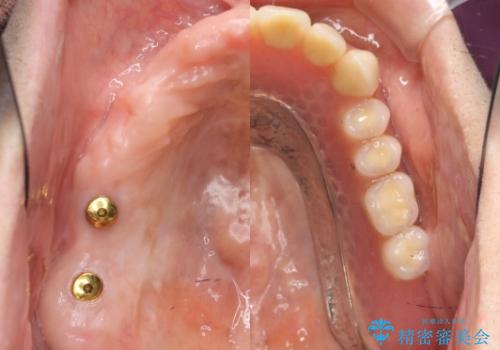

- 120万円(ストローマンインプラント×3・骨造成・チタンカスタムアバットメント×3・フルジルコニアクラウン×5)費用は治療当時の料金となります

連続した多数の歯の機能・審美回復にブリッジは設計上治療の手段になり得ない場合があります。

残された選択肢は入れ歯・インプラントになりますが審美性・咬合機能の回復度・快適さ・残存歯への負担は雲泥の差となります。